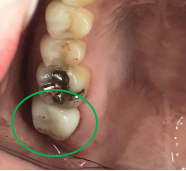

女性 Hさん 60代 (オールセラミック冠・インプラント)

主訴

右下のブリッジがゆらゆら動く。

治療内容

ブリッジの支台になっている奥の歯が、被せ物の中で虫歯になり、支台の役割を果たさず、前方の歯のみで支えられていました。前方の歯をそのままにして、後方の部分を切り離すと、そのまま取れてきました。中は、虫歯で歯根しか残っていない状況でした。この歯は、根管治療後、単独でオールセラミック冠を被せ、歯のないところにインプラントを埋入しました。

所感

今回の治療法には、次の3つの方法があります。

(1)虫歯になっていた歯の根管治療をし、土台を入れ、また再びブリッジにする。しかし、虫歯になっていたほうの歯は、ブリッジの支台として使うには、心もとなく長持ちしない可能性が高く、今度問題が生じたときには抜歯になる。

(2)虫歯になっていた歯に、単独で被せ物をし、歯のないところに1本だけの部分入れ歯を入れる。取り外しの入れ歯なので、自分の歯のような感覚で噛むことはできない。この方法も歯のない部分の負担を欠損の両側の歯に負担してもらうため、長持ちしない可能性が高い。

(3)虫歯になっていた歯に、単独で被せ物をし、歯のないところにインプラントを埋入する。欠損している部分の負担を前後の歯に負担させないので、歯を守ることができる。また、自分の歯と同じ感覚で食事をすることができる。

患者さんは、3つ目の方法を選択されました。一番長持ちし、これ以上歯を失わないためには、最良の方法だと考えます。

オールセラミック冠(失活歯):¥104,500(税込)

インプラント:¥363,000(税込)

合計:¥467,500(税込)

Before

冠の中で大きな虫歯になり支台の役割を果たしていませんでした。

【インプラント埋入前】

冠はブリッジを切断しただけで取れてきました。軟化象牙質を取り除いたところ、歯根しか残っていない状況で保存できるかどうかのぎりぎりのところでした。

After